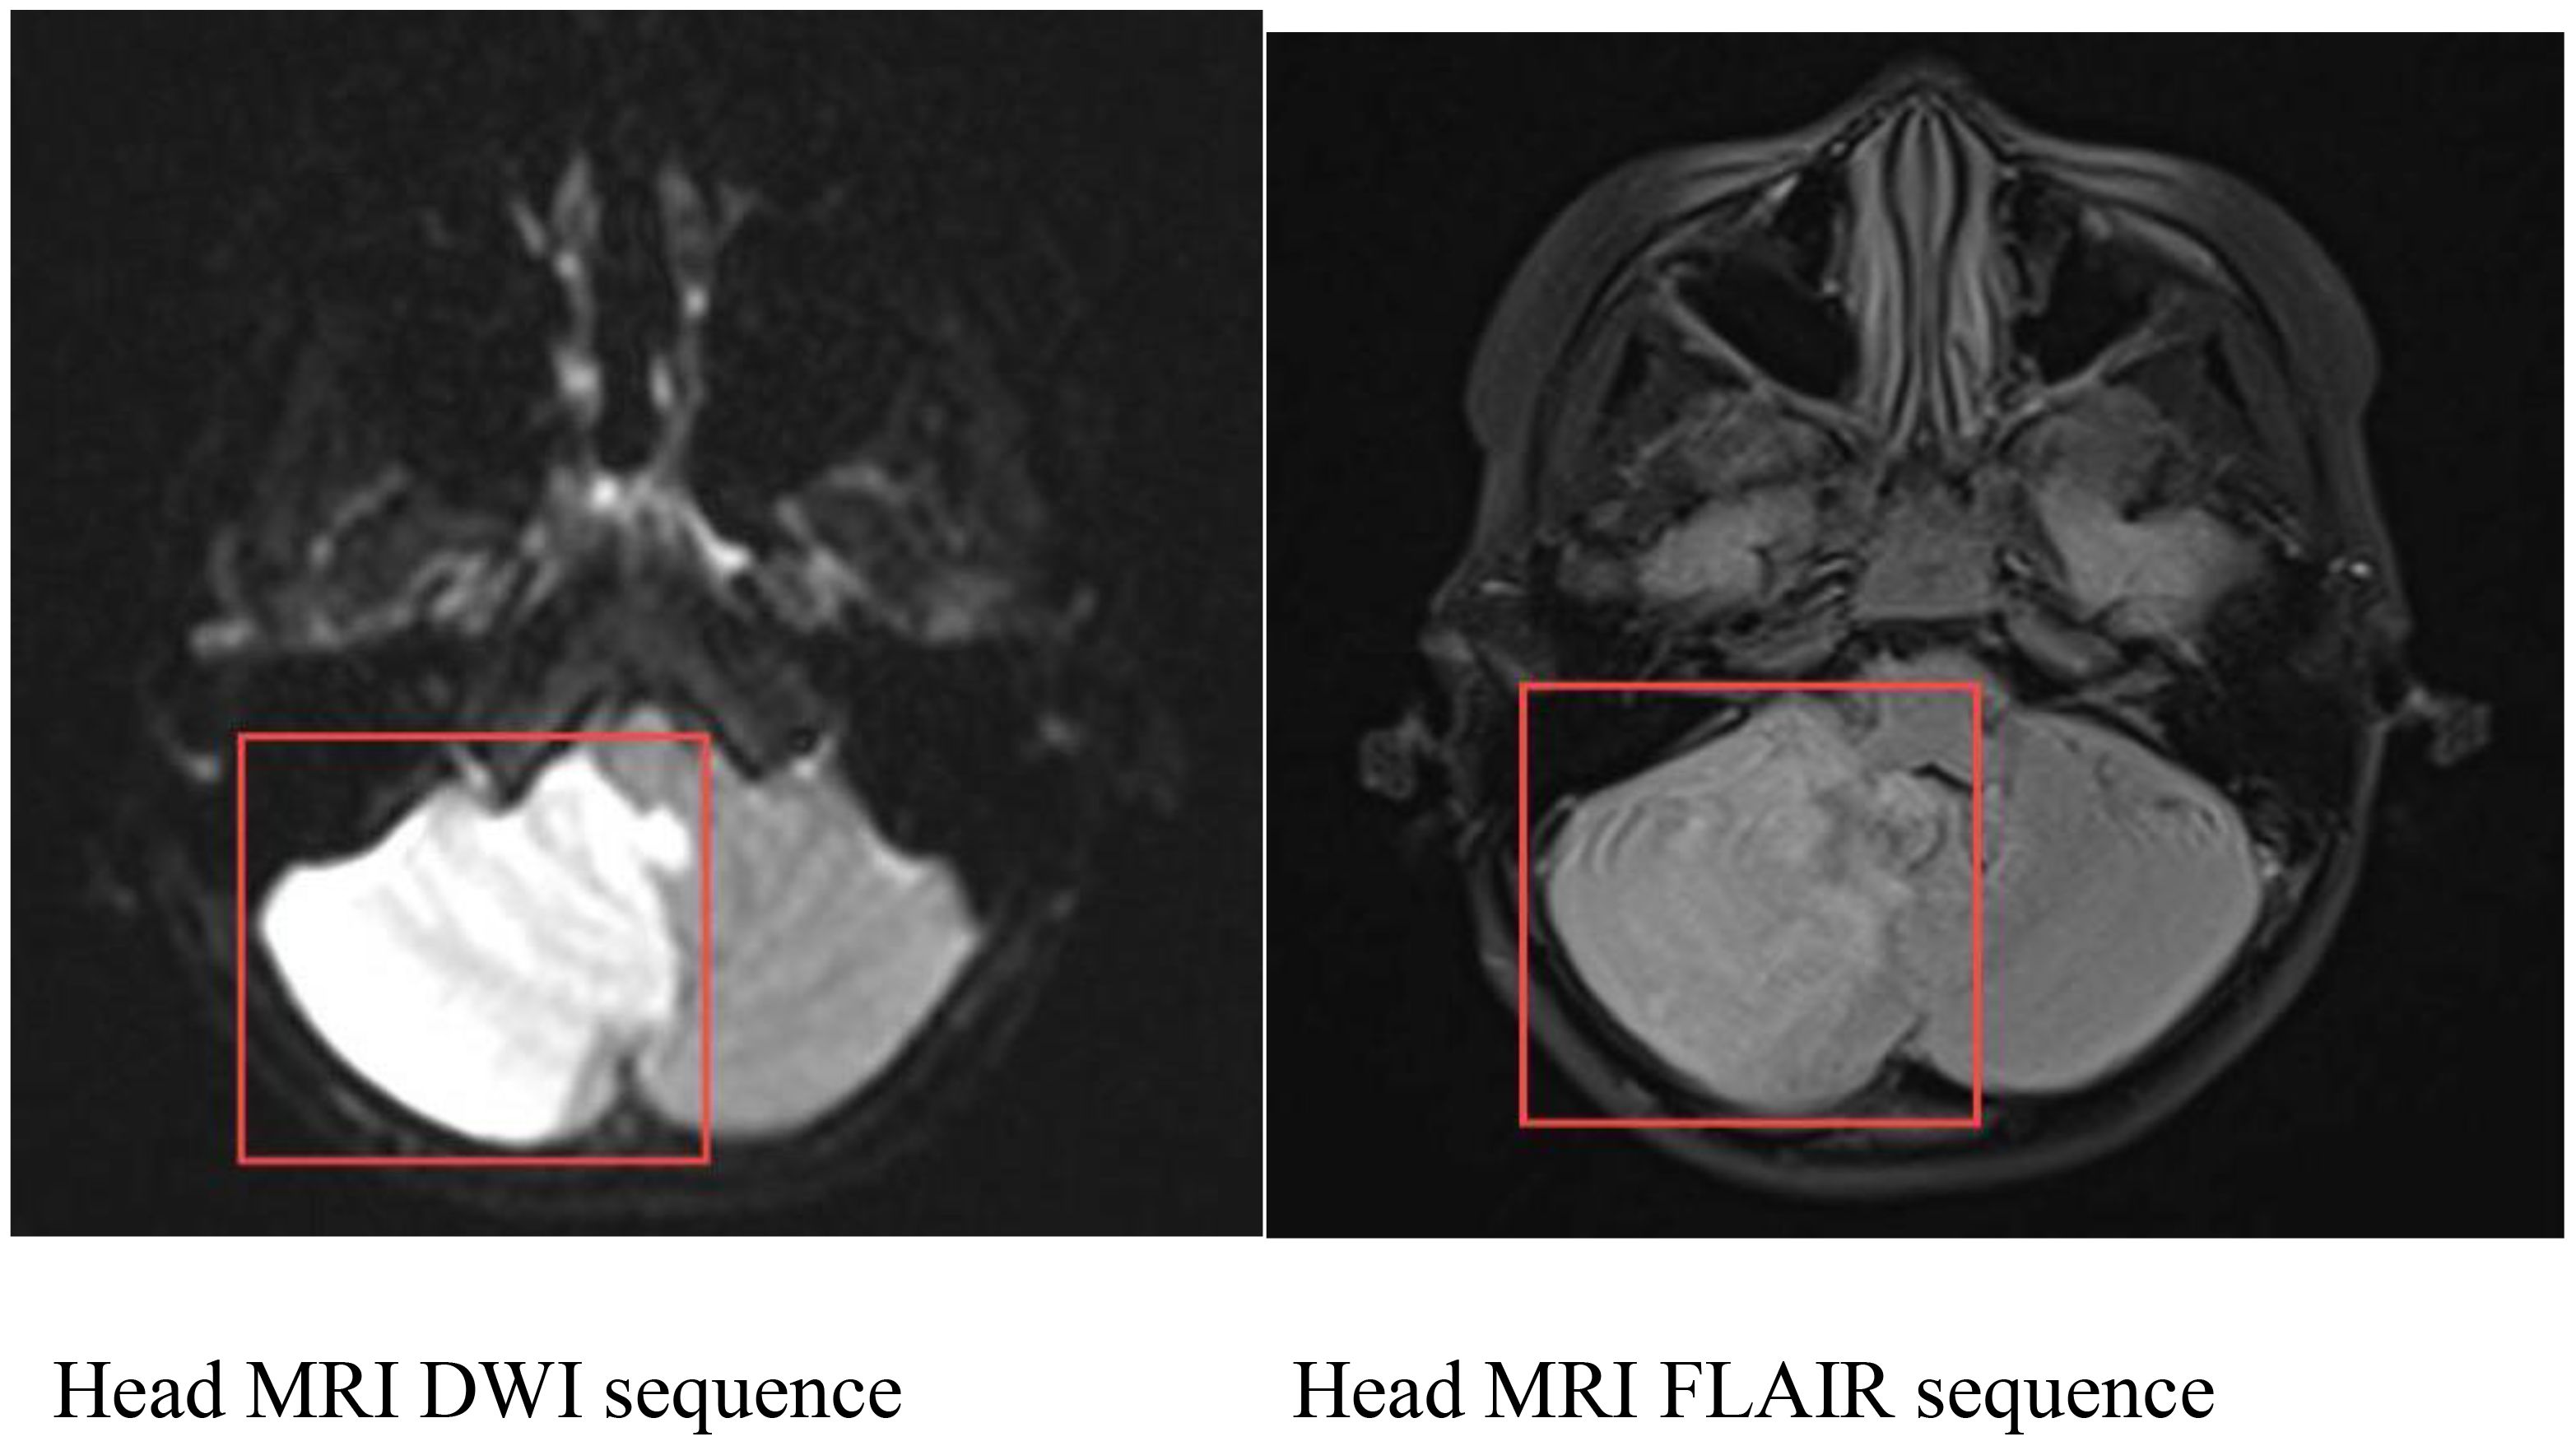

Objective This case report presents a pediatric case of eosinophilic granulomatosis with polyangiitis (EGPA) presenting with cerebella infarction as the initial symptom. The study aims to summarize the clinical features and treatment advancements of this condition, enhancing clinicians 'understanding and reducing misdiagnosis and missed diagnosis. Methods A 9-year-old male patient admitted to the Rheumatology Department of Anhui Provincial Children's Hospital was evaluated for "Dizziness, vomiting for one day, and consciousness impairment for half a day." The patient had recurrent bilateral lower limb rashes and asthma attacks over the past year. Blood tests revealed elevated eosinophil levels and IgE antibodies, while bone marrow cytology showed increased eosinophil counts. Brain MRI demonstrated cerebral infarction, herniation, and suspected thrombosis, with skin biopsy confirming vasculitis characteristics. Through retrospective analysis of clinical data and literature review, this study comprehensively summarizes EGPA's clinical features and treatment progress. Results The patient presented with cerebella infarction as the initial symptom, accompanied by central nervous system involvement, skin manifestations, hematological disorders, and vasculitis. With a history of asthma attacks, eosinophil counts during hospitalization peaked at 4.9×10^9/L (compared to baseline levels>1×10^9/L). After thorough evaluation for infections, malignancies, diffuse connective tissue diseases, immunodeficiency disorders, and inherited metabolic disorders, EGPA was confirmed. Treatment included anti-inflammatory steroids, cyclophosphamide (CTX) induction therapy, anticoagulation, followed by mycophenolate mofetil (MMF) maintenance at therapeutic doses, supplemented with rituximab. Current follow-up shows normalized eosinophil counts, restored muscle strength, resolution of skin rashes without recurrence, and favorable clinical response. Conclusion EGPA presents diverse clinical features. Cerebella infarction as the first neurological manifestation in children is rare. Eosinophilia serves as a characteristic feature. When pediatric asthma patients exhibit neurological symptoms, EGPA should be considered. For cases with central nervous system involvement, combined steroid therapy with cyclophosphamide pulse induction proves effective.